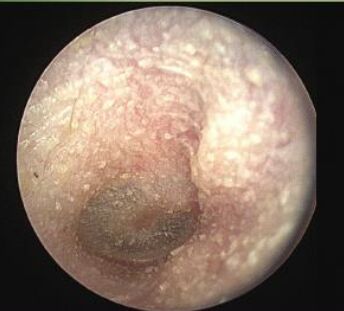

20.一中年男性長年四季晨泳,耳鏡檢查發現如圖,下列何者為最可能之診斷?

(B)exostosis

Exostoses, sometimes called surfer's ear, are bony overgrowths in the ear canal.

Exostoses are most commonly found in people with a history of cold water exposure.

Multiple smooth, round, bony overgrowths are seen, and often in both ears.